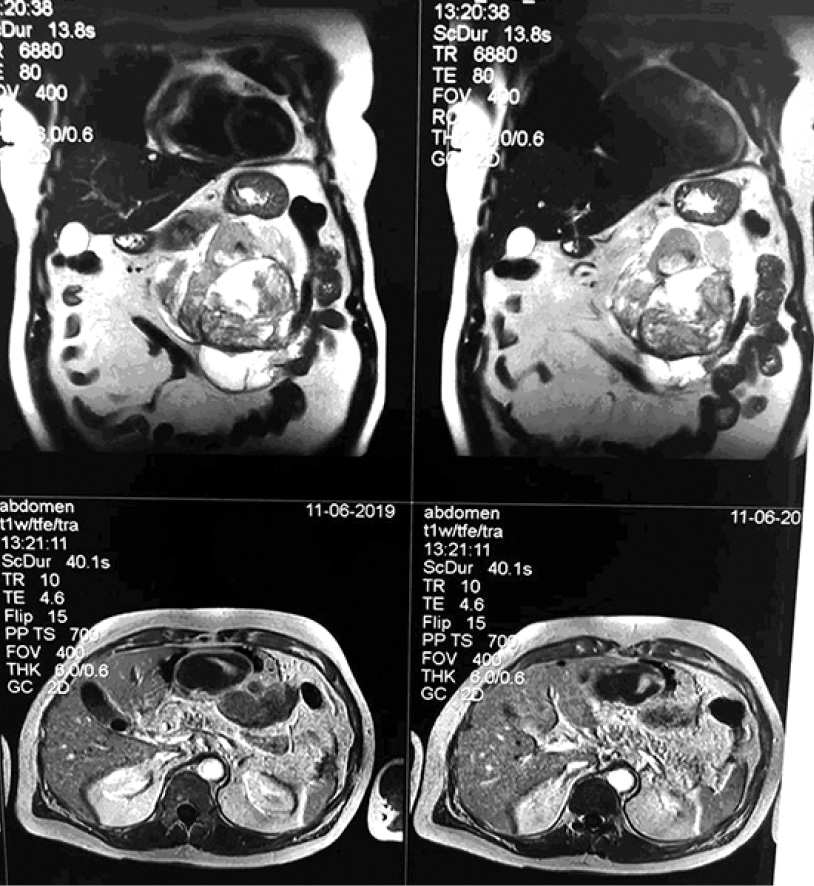

- МРТ с контрастированием от 11.06.2019 г. Заключение: Объёмное образование брюшной полости слева, кистозно-солидной структуры со сдавлением желудка (tumor). Множественные кисты обеих долей печени. Конкремент желчного пузыря. Увеличенные забрюшинные лимфатические узлы (рис. 1–4).

Рис. 1. Увеличенные забрюшинные лимфатические узлы

Рис. 2. Увеличенные забрюшинные лимфатические узлы

Рис. 3. Увеличенные забрюшинные лимфатические узлы

Рис. 4. Увеличенные забрюшинные лимфатические узлы